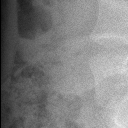

右肺下野钙化灶

肺挫伤